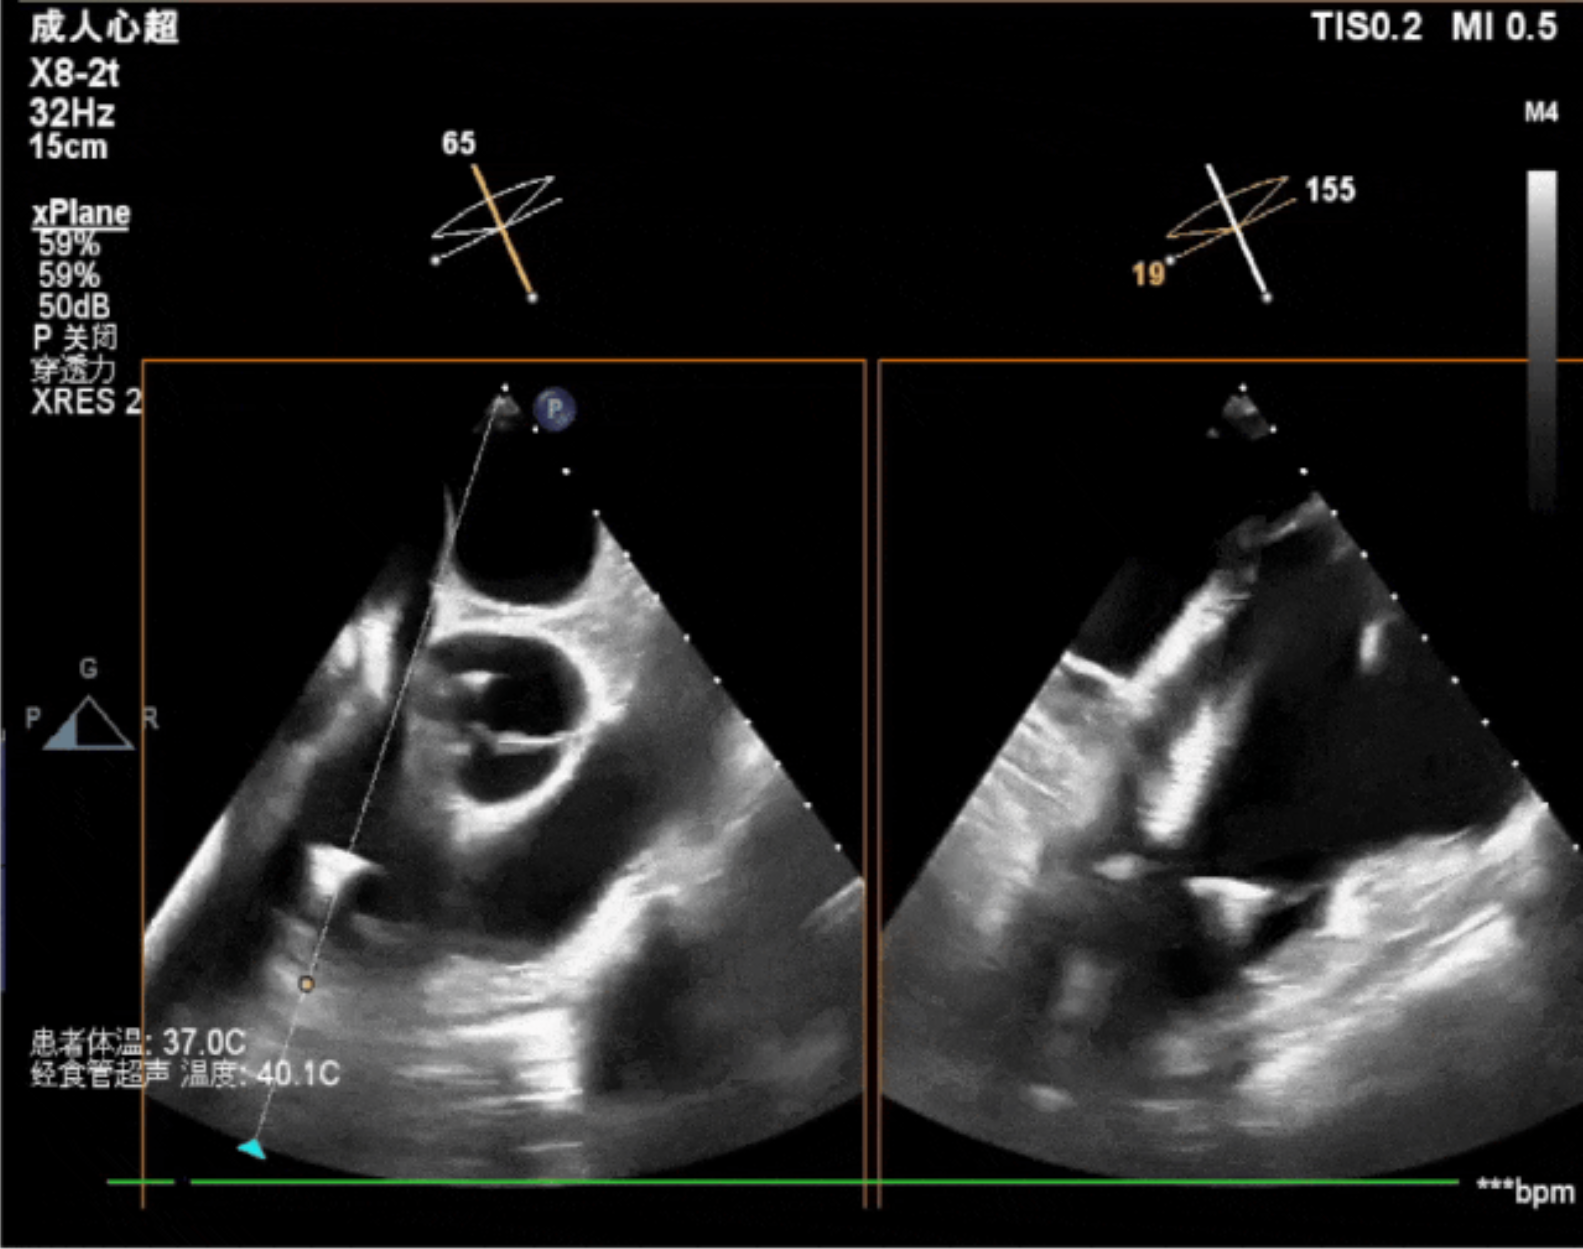

術中經食道超聲輔助下可見LuX-Valve Plus夾持件抓捕瓣葉狀態(tài)良好,夾持件在位,室間隔錨定位置良好,假體瓣膜整體錨定狀態(tài)穩(wěn)固。

術后即刻經食道超聲可見,三尖瓣假體瓣膜位置合適,牛心包瓣葉運動狀態(tài)良好,開閉正常,瓣周及瓣葉對合緣處未見明顯返流,心電圖及心包狀態(tài)較術前無明顯變化。

本次直播手術中,手術團隊在超聲與DSA等多維影像手段的支持下,精準嫻熟的完成LuX-Valve Plus瓣膜的植入,器械操作時間僅為30分鐘,瓣膜植入后術中即刻三尖瓣返流消失,多普勒超聲下無明顯瓣周漏或中心性返流,肺動脈壓正常,平均跨瓣壓差僅為1mmHg,人工瓣膜運動正常,術后1小時內該患者即安返病房。

今天我們見證了一臺嫻熟、優(yōu)雅且迅速的經導管三尖瓣置換手術,我們可以看到的是,手術完成后的三尖瓣超聲指標非常完美,值得一提的是,經食道超聲技術在整臺手術中有著非常重要的作用,我們可以用幾個簡單的切面精準的指引LuX-Valve Plus的植入,相信在未來,超聲在三尖瓣介入置換圍術期中將有著更重要且成熟的應用。